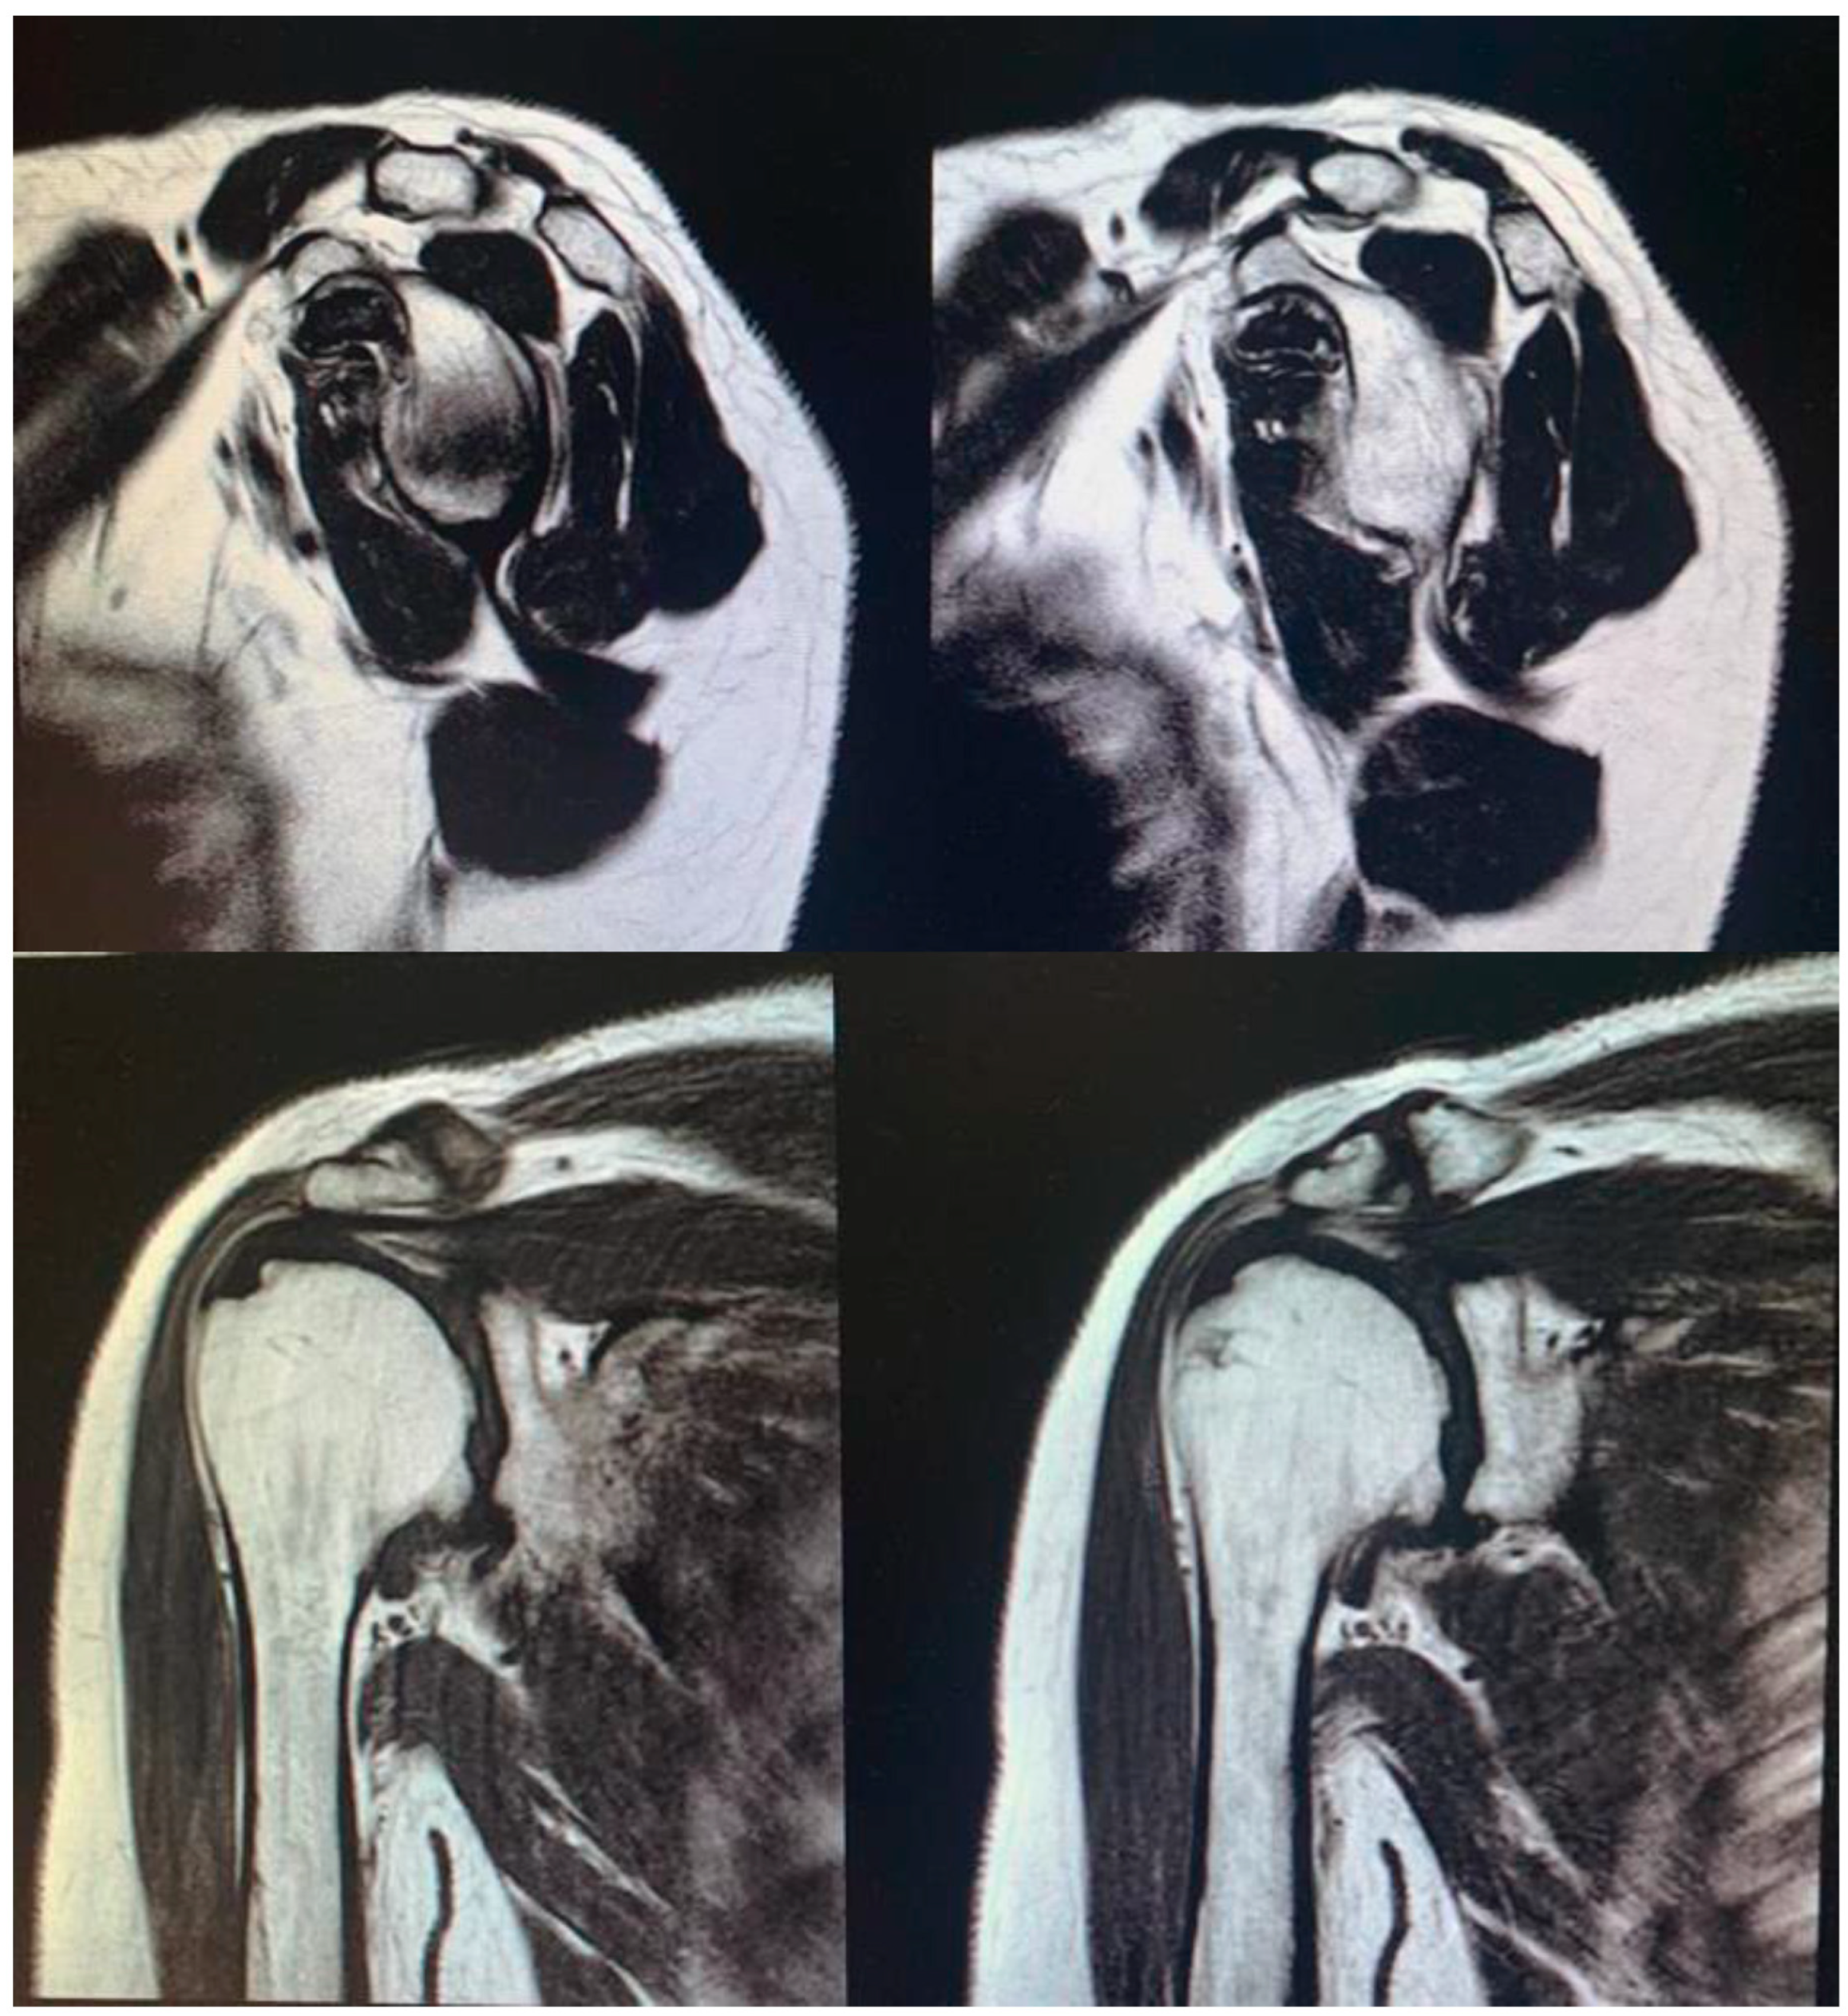

Surgical procedure. All surgeries were performed by the senior Author (S.G.), implanting a Durom Shoulder Cup (Zimmer Biomet, Warsaw, IN, USA), a Copeland Humeral Resurfacing Head Surgery (Zimmer Biomet, Warsaw, IN, USA) or a SMR Resurfacing Shoulder Prosthesis System (Lima Corporate, Udine, Italy). All patients were pre-operatively evaluated through a clinical examination, plain radiographs in the antero-posterior and axillary views, a computed tomography scan, and magnetic resonance imaging (Figure 3), in order to determine the correct indication to HRA.

Figure 3. Pre-operative magnetic resonance imaging to evaluate the integrity of the rotator cuff and the correct indication for an HRA.